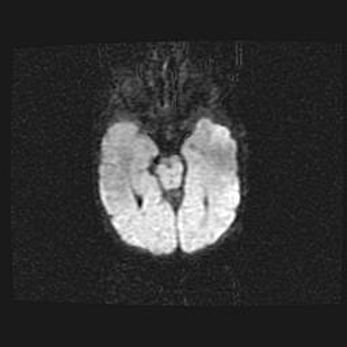

Аномалия Денди-Уокера. Признаки гипоплазии мозолистого тела.

Возраст: 5 месяцев 3 дня

Вес: 5550 г

Пол: мужской

Окружность головы: 39 см

Срок гестации: 40 недель

Аномалия Денди-Уокера – это порок развития головного мозга, для которого характерна триада симптомов: гипотрофия или аплазия червя мозжечка и/или полушарий мозжечка, расширение четвёртого желудочка с формированием ликворной кисты задней черепной ямки, гипертензионная гидроцефалия различной степени.

Гипоплазия мозолистого тела относится к дефектам внутриутробного этапа развития мозговой ткани, возникающим в процессе закладки структур головного мозга, что происходит на начальных этапах развития эмбриона.